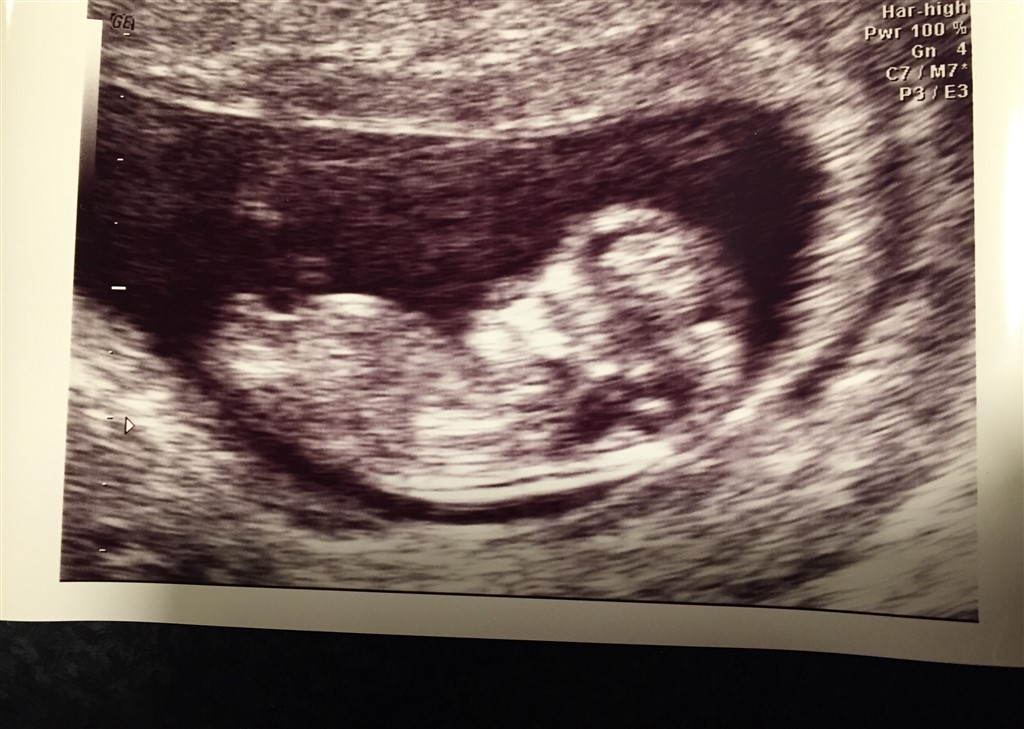

Jeg er idag 12+0, og har endnu ikke været til NF men blev skannet 10+6. Det er vist noget om at man kan gætte kønnet udfra hvilken vej tappen vender - som på det viste billede. Så her på en kedelig mandag aften, så håber jeg i vil gætte lidt sammen med mig. Det er 3. barn og vi har i forvejen 2 piger. ��

I følge det du har lagt op her tror jeg det bliver en dreng

Heh, jeg syntes det ligner en pige

Jeg glæder mig - der er ret blandede meninger, kan jeg se. Tror selv det er en pige.